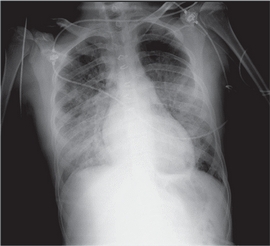

Se transfundieron dos concentrados de hematíes durante la cual aumentó el trabajo respiratorio con hipoxemia y saturación de O2 72%. No hubo respuesta a oxigenoterapia de alto flujo y requirió ventilación mecánica. En la radiografía de tórax se observaron opacidades pulmonares bilaterales y difusas sin cardiomegalia (Figura 2), siendo la radiografía previa a la transfusión normal. El electrocardiograma y el ecocardiograma descartaron la posibilidad de miocardiopatía.

Ante la sospecha de TRALI basada en la relación temporal entre la clínica respiratoria y la transfusión con la presencia de infiltrados pulmonares bilaterales difusos y la falta de síntomas de sobrecarga circulatoria, se inició tratamiento esteroideo y se suspendió la transfusión (lo cual se comunicó al Servicio de Hematología) y se aplicó el protocolo de nuestro centro sobre eventos relacionados con la transfusión. El producto sanguíneo se regresó al banco de sangre para iniciar la investigación.